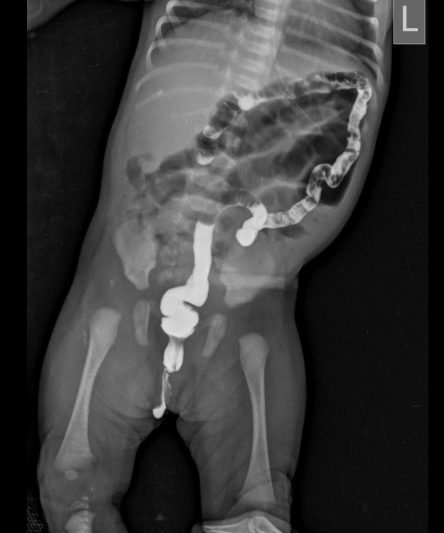

Microskan with Ultra high frequency can take the Lateral Lumbar Spine image of a 90 kg Patient with the correct image receptor